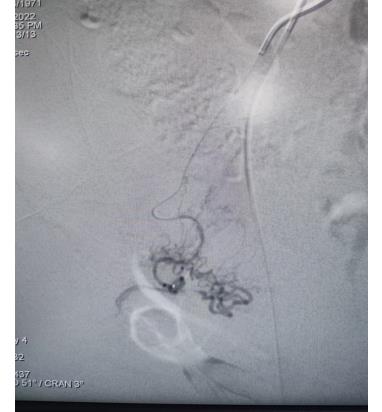

但患者還有子宮肌瘤長年不規(guī)則出血,支架術后需要抗凝、抗血小板聚集治療,這樣加重了子宮異常出血;半年前患者因長期子宮出血不止導致重度貧血進行輸血治療,為此患者痛苦不堪;經過詳細檢查患者合并有子宮肌瘤,經過崔旭輝主任認真研判,考慮絕經期女性,該患者目前最佳選擇是行子宮動脈栓塞術。

子宮動脈栓塞術屬于血管介入性治療,方法是于股動脈穿刺進針插入導管,在X射線造影下定位進入兩側子宮動脈,注入栓塞劑完全栓塞子宮動脈,從而達到止血或讓子宮肌瘤和病灶缺血壞死的目的;2022年12月6日,在崔旭輝主任、孟慶槐副主任醫(yī)師、馬力主治醫(yī)師等我院介入團隊協(xié)作下,成功為患者進行了雙側子宮動脈栓塞術,術后患者子宮異常出血停止,效果立竿見影,患者病情恢復良好。

左側子宮動脈栓塞前后對照

右側子宮動脈栓塞前后對照